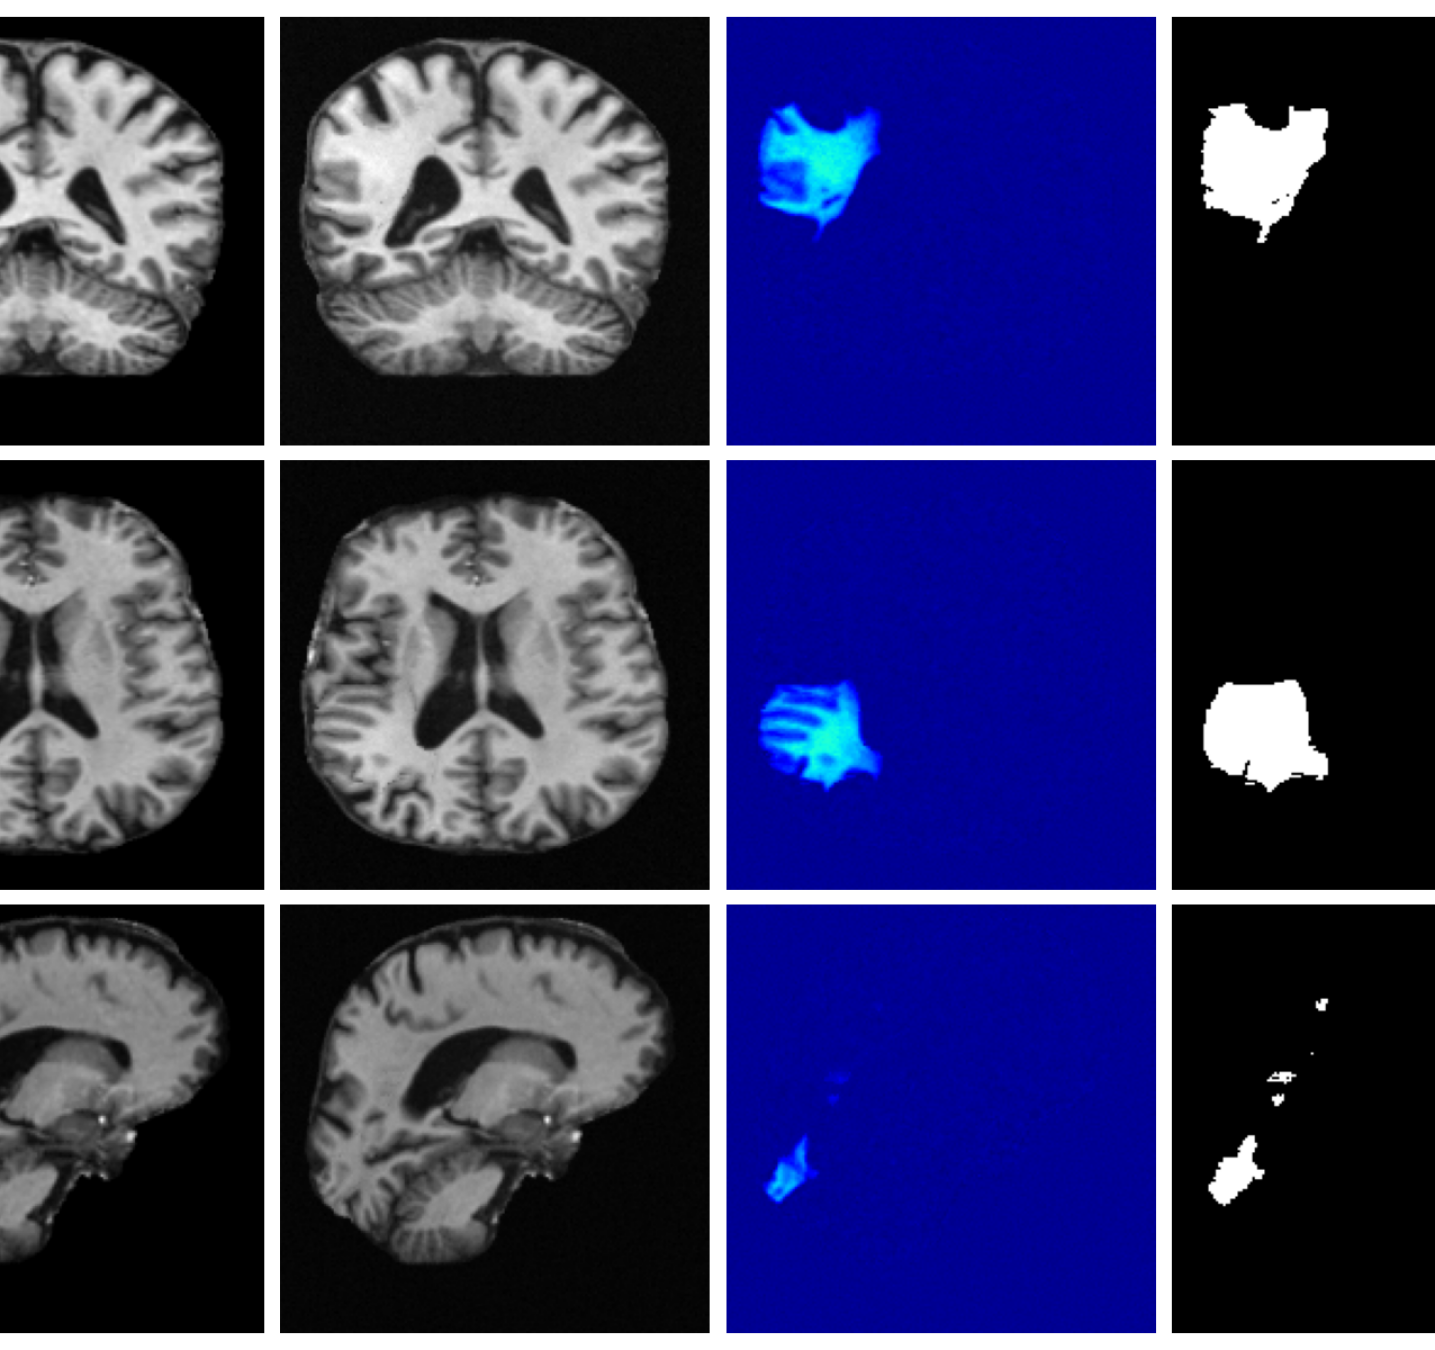

Qualitative T1w results are shown in Figure 2, with further examples for other modalities in Appendix A.8. LoHiResGAN and Res-SRDiff produce unrealistic images with severe artifacts, likely arising from bias fields, sharp intensity artifacts, and other noise not present during training. UniRes generates oversmoothed images, likely due to its TV prior and its reliance on information from multiple input modalities, whereas we apply it unimodally. Di-Fusion shows less pronounced but still notably blurry, voxelated reconstructions which lack the fine-grained details generate by our method. This is likely, in part, due to our use of synthetic rather than real noisy training data, which the method was designed for. As such data is scarce, and in our case unavailable, this requirement represents a significant limitation of Di-Fusion. SynthSR, whilst not as well as our method, does preserve key anatomical structures. However, our difference maps show reduced contrast, further supporting the strong quantitative results shown in Table 2.

Figure 3 (additional examples in Appendix A.9) shows that SynthSR preserves healthy tissue but struggles with large lesions, while DDPM-2D and DDPM-3D, despite producing high-contrast anomaly maps, generate unrealistic homogeneous inpainting, consistent with their lower performance in Table 3. In contrast, our method yields the most anatomically plausible inpainted regions, although anomaly maps appear subtle due to low contrast between lesions and healthy tissue.

A.8 Additional qualitative restoration results

Additional qualitative results for the Clinical dataset are given in Figures 7, 8 and 9, and for the Low-field dataset in Figures 10 and 11.

A.9 Additional qualitative inpainting results

Additional qualitative results for the ATLAS and BraTS datasets are given in Figures 12 and 13, respectively.